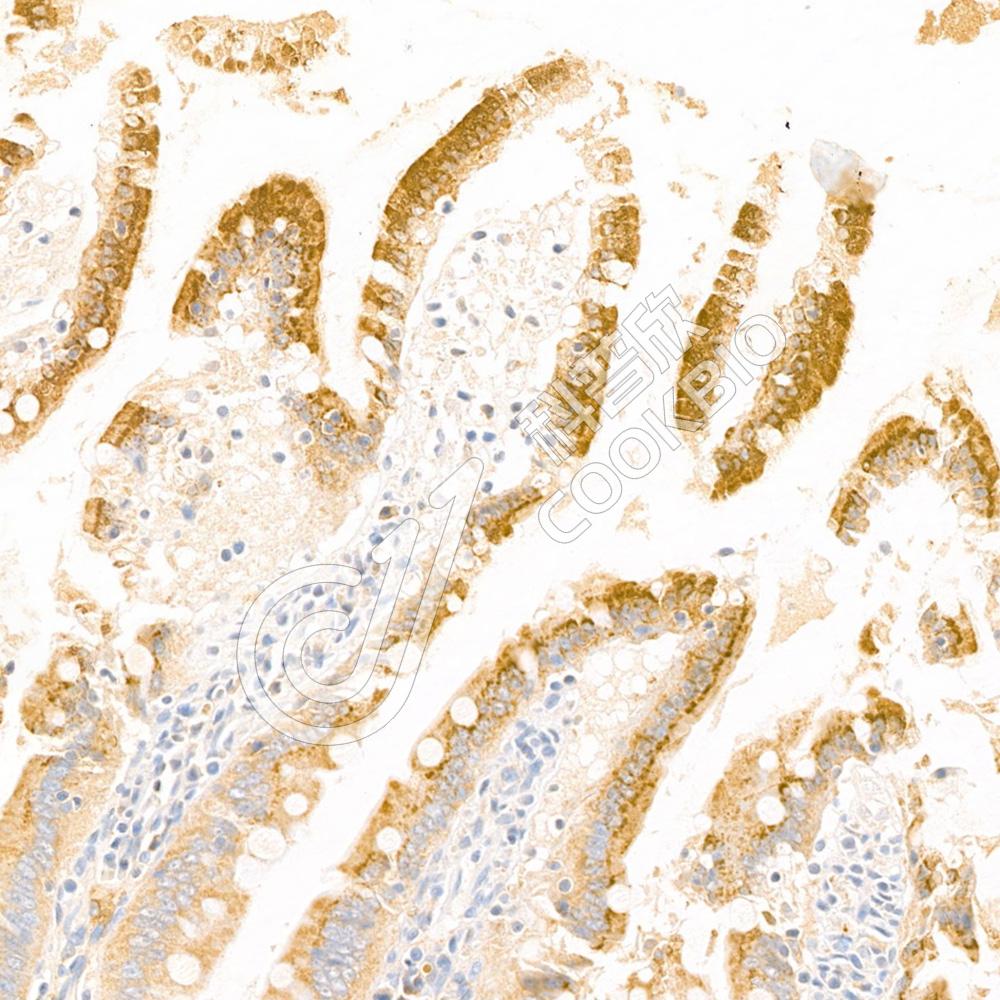

IHC检测APOA4/Apo-AIV蛋白(货号 K1334308).

样品: 小鼠小肠, 4%多聚甲醛 (货号KSG1101) 固定12-24小时.

抗原修复: 柠檬酸抗原修复液(干粉, pH 6.0) (KSG1201), 98℃, 20分钟.

—抗: 1: 1300稀释, 4℃ 孵育过夜.

二抗: S-vision免疫组化多聚二抗(山羊抗兔),即用型 (货号KB3906), 室温孵育20分钟.

样品: 大鼠小肠, 4%多聚甲醛 (货号KSG1101) 固定12-24小时.